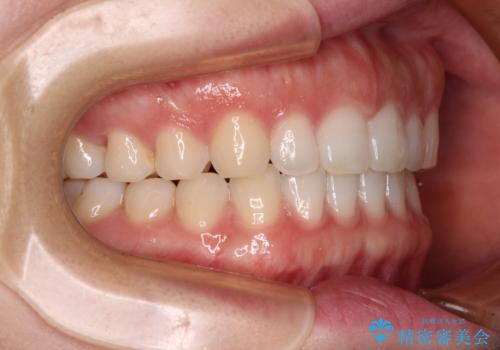

すきっ歯とオープンバイト インビザライン・ライトで改善

- 食いしばりによる顎の負担を気にして来院された患者様です。

当初は、ボツリヌス毒素による咬筋の過緊張の緩和と、睡眠時のマウスピース装着による咬合負担の解消を行いました。

オープンバイトのため、奥歯に負担のかかる咬合状態であったので、矯正治療を提案したところ、希望をされました。

すきっ歯程度の軽度の歯列不正であったため、インビザライン・ライトにより咬合改善を行うこととしました。

オープンバイトやすきっ歯は、舌突出癖によりあっという間に後戻りをするため、矯正治療前からトレーニングを行っていただき、更には後戻り防止のワイヤーリテーナーを併用しています。